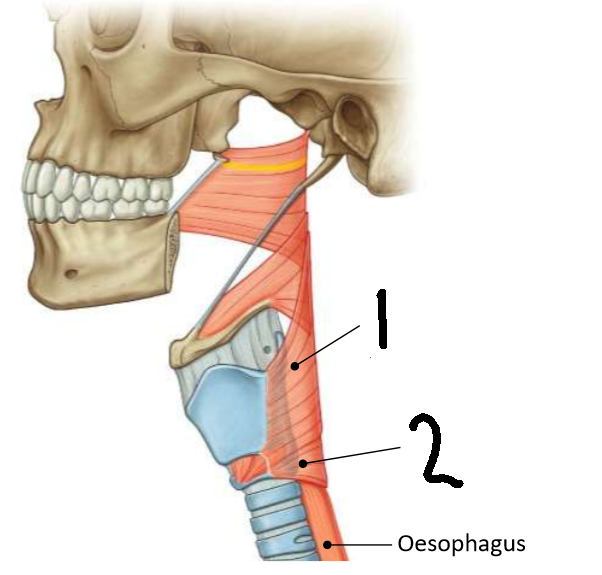

What muscle is this?

inferior constrictor

Which part of the muscle is 1?

thyropharyngeus

Which part of the muscle is 2?

cricopharyngeus

What are the attachments of this muscle?

oblique line of thyroid cartilage, cricothyroid tendon, cricoid cartilage → pharyngeal raphe